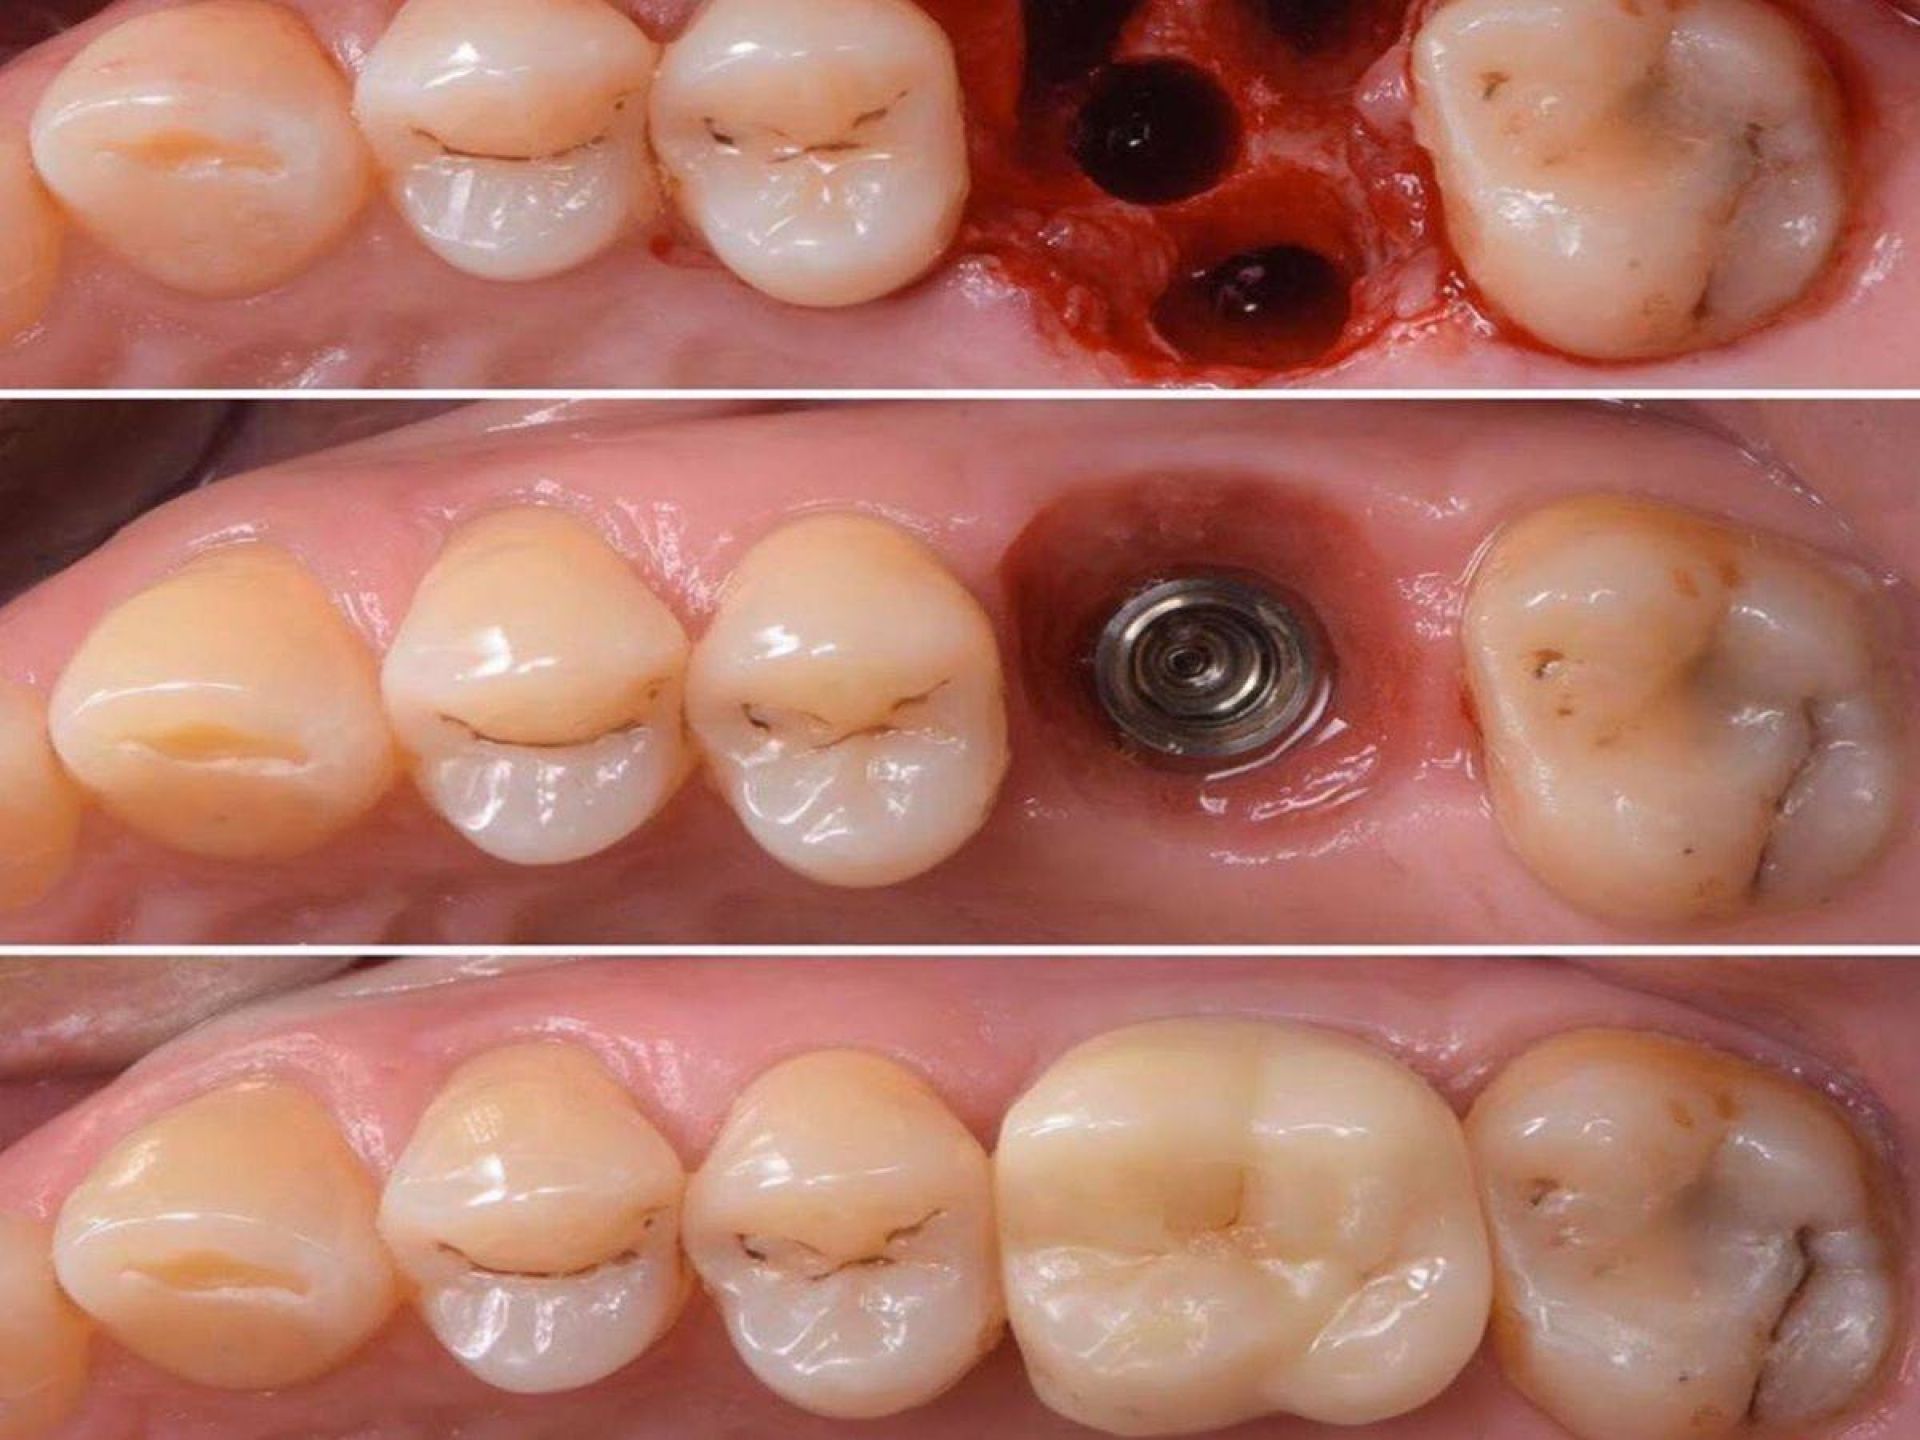

- одномоментно видаляти зуб та встановлювати імплант з подальшим протезуванням коронкою;

Імплантація - складний процес, який відбувається в декілька етапів:

- безкоштовна консультація, підготовка

- операція

- післяопераційний період (зростання кістки)

- кріплення абатменту

- встановлення коронки

Імплантація - довготривалий процес, який може становити декілька місяців. Все залежить від індивідуальних обставин, та процесу загоєння

Імплантація полягає у встановленні штучного зубного кореня та відновленні коронки за допомогою ортопедичної конструкції. Операція виконується під анестезією, що робить її абсолютно безболісною. Процес відновлення після операції відбувається швидко, що дозволяє вам швидко повернутися до звичайного життя.

Однією із переваг, які пропонує «Стоматологія Олексюка», є негайна імплантація. Цей метод дозволяє встановити імплантат безпосередньо після видалення пошкодженого зуба. Такий підхід гарантує високу точність і швидке відновлення, оскільки кістка ще не зазнала деформацій.